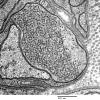

PERIPHERAL NEUROPATHY

5 AXONAL REGENERATION (7)